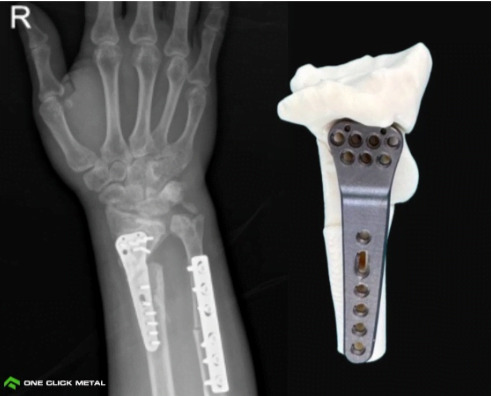

Her hastanın anatomisine göre tasarlanan özel implantlar daha iyi uyum, daha

yüksek stabilite ve daha kısa cerrahi süre sağlar. Bu özellik; travma vakalarında, şekil

bozukluklarında ve düzeltme ameliyatlarında büyük önem taşır. - Kemik ile İmplant Arasında Doğrudan Biyolojik Bağlantı Oluşması İçin